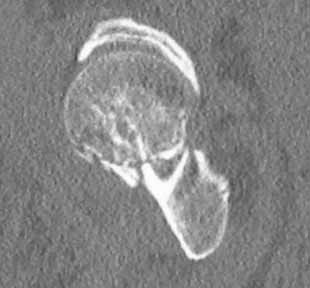

Бедро одномоментно делать не стал, не было уверенности в наличии перелома на уровне шейки. Во время операции смотрел тазобедренный сустав под ЭОПом,

головка неподвижна. После операции повторили КТ, стало очевидно, что имеется субкапитальный перелом. Что делать, остесинтез или протезирование? Если остеосинтез, то чем? Заранее благодарен за советы.